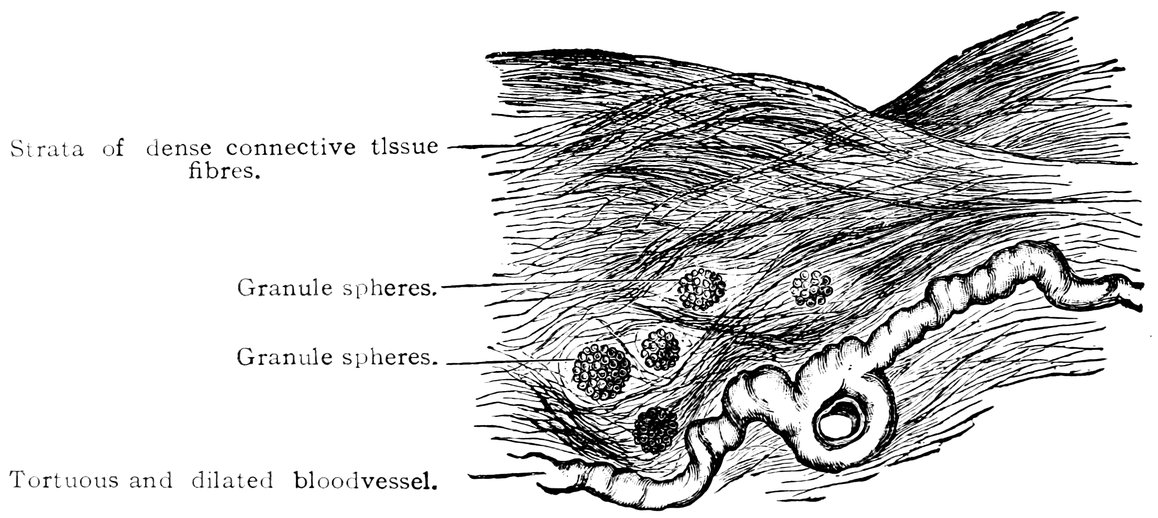

| 17. | Graafian follicles | 62 |

We must first consider the changes in the ovaries, which play an etiologically important part. At the onset of puberty, the follicular masses of the ovary exhibit a more active growth, the follicles increase in size, with their contained ova they approach the surface, and finally, by the bursting of the follicles, the ova are extruded. Then, in the life-phase in which conception occurs, and under the influence of the hyperæmia of all the pelvic viscera that accompanies this process, a notable development of the corpus luteum takes place, this latter body reaching its maximum size in the eleventh week of pregnancy, subsequently undergoing involution and leading to the formation of a considerable scar. Finally, in the critical period of life in which the menstrual flow ceases, a continually increasing growth and new formation of connective tissue-stroma takes place in the ovaries at the expense of their cellular constituents, and a regressive metamorphosis of the graafian follicles occurs.

In association with these sexual processes there ensues a series of striking changes in the shape and consistency of the ovaries, affecting both the surface and the parenchyma of these organs, and capable of stimulating the nervous ramifications in their tissue. In this connection it is worthy of note that the branches supplying the ovaries from the spermatic plexuses of the sympathetic contain a considerable proportion of sensory fibres.